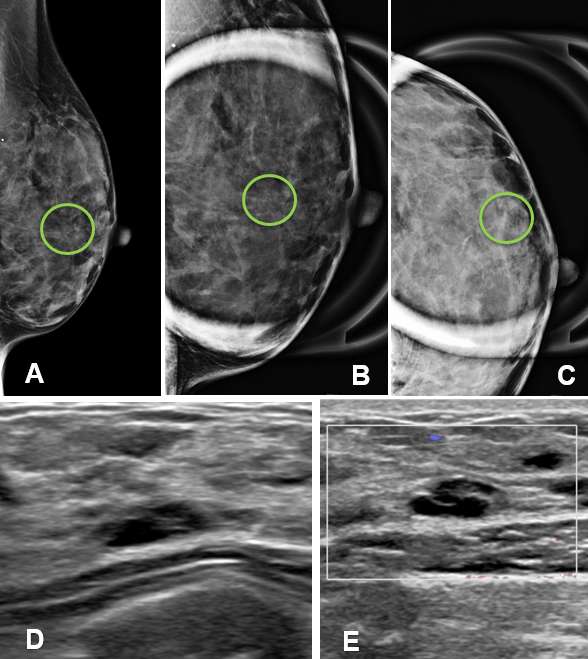

Complicated Cyst

Complicated cysts are “probably benign” lesions as they contain internal debris which may mimic a solid mass appearance on imaging. The internal debris typically represents proteinaceous or hemorrhagic material which needs to be carefully evaluated in order to differentiate a complicated cyst from a complex cyst, which have malignant potential. Management of complicated cysts is dependent on the degree of suspicion and can either be closely followed with short-term interval imaging or undergo aspiration and/or biopsy for definitive diagnosis.

Ultrasound - On ultrasound, complicated cysts appear as round or oval lesions with thin walls, homogeneously hypoechoic internal debris, and may exhibit fluid-debris levels and low-level internal echoes that can change the shape of the cyst with changes in patient positioning. The internal debris may appear as hyperechoic components that adhere to the cyst wall and careful examination with power Doppler should be performed to exclude vascularity which would indicate a solid component. Complicated cysts may or may not exhibit posterior acoustic enhancement depending on the make-up of its internal components. The walls of a complicated cyst are often slightly thicker than that of simple cysts due to inflammation or mild fibrosis which can occur due to the internal proteinaceous or hemorrhagic components.

Mammography - Complicated cysts appear as well-circumscribed round, oval or slightly lobular, relatively low-density masses which may exhibit milk of calcium (layering) and rarely rim calcification.